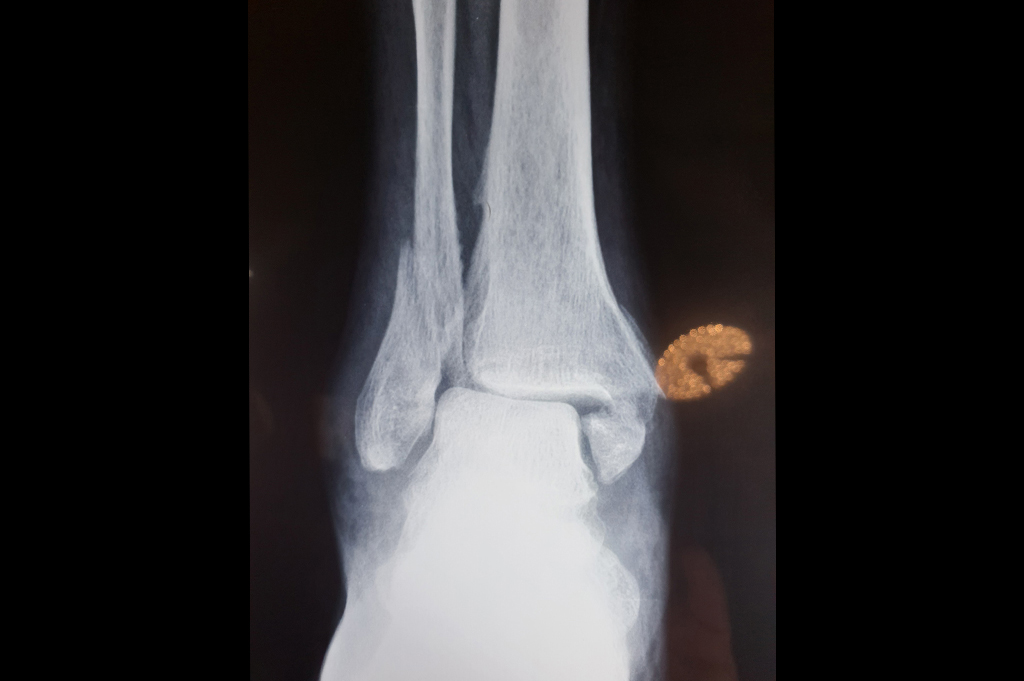

Ankle